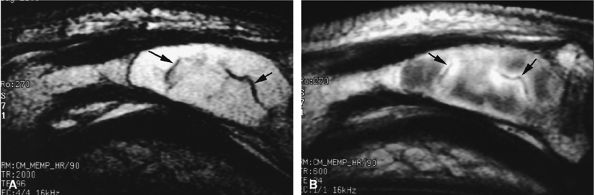

FIGURE 11.142 ● Osteoarthritis of the PIP joint on (A) a coronal proton density fat-suppressed image and (B) a sagittal post-contrast fat-suppressed T1-weighted image. Erosive osteoarthritis with foci of subchondral bone edema (asterisks), a bone cyst (arrowheads), and capsuloligamentous thickening (black arrows) are seen. A possible thin channel between the cyst and the joint (white arrow) or diffuse synovitis (small circles) may also be seen.